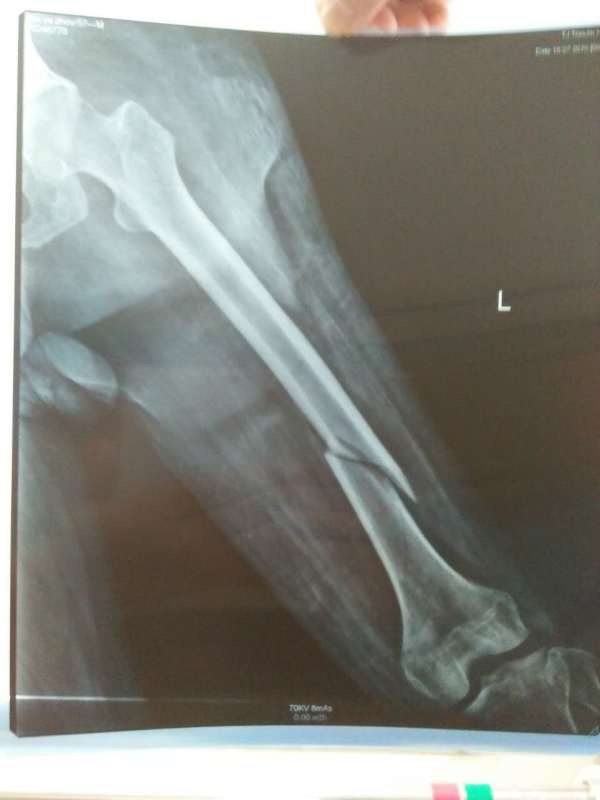

父亲大腿骨折~因为左侧腿有小儿麻痹,无法做手术~一直做的牵引,现出院在家做牵引~父亲大腿骨折~因为左侧腿有小儿麻痹,无法做手术~一直做的牵引,现出院在家做牵引~下面还需要继续牵引吗?还需要后续什么措施吗?片子附上~请大家帮我看一下~非常感谢

对位对线不良,还是要继续牵引直到长愿蛋出潜耻骨痂长结实为止。 有些主要下肢肌肉肌力正常的小儿麻痹症患者,手术还编印最是可进行的。